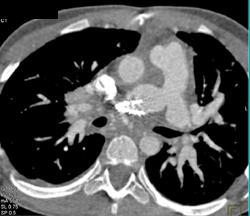

Type A Dissection